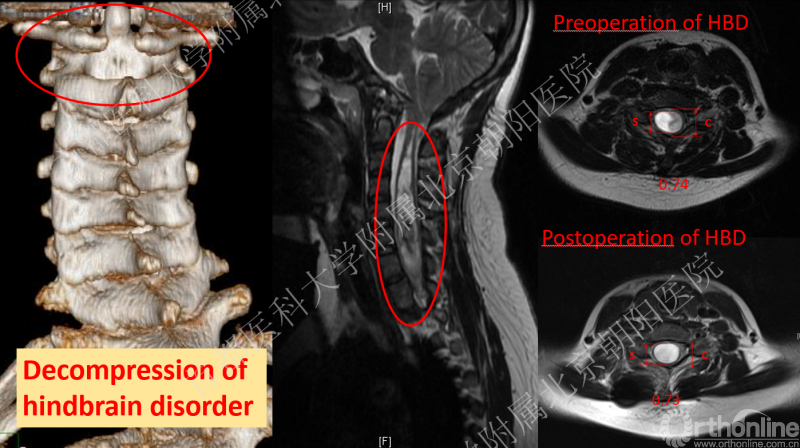

这位15岁的女性患者于北京朝阳医院就诊后,先行皮肤牵引治疗,牵引后腰痛症状加重,于是建议患者先行后颅窝减压术HBD,术后6月再进行脊柱侧凸矫形。HBD术后,患者的空洞在MRI影像上虽然无明显缩小,但术前牵引并未使患者的腰痛症状加重,也没有引起其他神经功能异常表现,于是海涌教授团队对这位患者成功实施了脊柱侧凸三维矫形手术治疗。

目前,患者矫形效果满意,腰痛症状缓解,术后随访1个月也没有出现神经功能异常,空洞在MRI的表现与此前相同,现仍在密切随访关注中。

患者进行HBD后颅窝及空洞变化情况